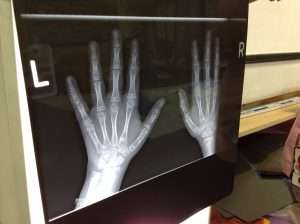

We enjoyed looking at x-rays and also dressing up as doctors and nurses.